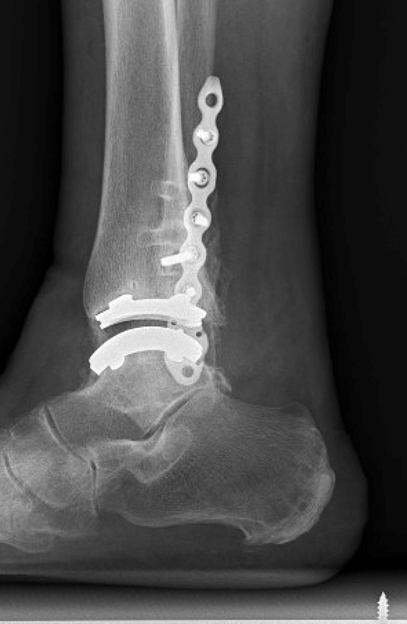

TOTAL ANKLE REPLACEMENT :: ORIF CALCANEUS :: ORIF ANKLE FRACTURE DISLOCATION :: COMPLEX BUNION AND LESSER TOE CORRECTION :: TALUS FRACTURE -1 :: TALUS FRACTURE -2 :: LISFRANC REPAIR :: COMPLEX TRIPLE ARTHRODESIS 1 :: COMPLEX TRIPLE ARTHRODESIS 2 :: MINIMALLY INVASIVE BUNION REPAIR 1 :: MINIMALLY INVASIVE BUNION REPAIR 2 :: ARTHROSCOPIC CARTILAGE REPAIR :: TENEX SPUR DEBRIDEMENT :: Haglunds Debridement and Achilles Repair